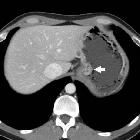

Perirenal

neoplastic recurrence from adenocarcinoma of the gastric cardia. After neoadjuvant chemotherapy, CT with gastric distension (oral water) and hypotonisation showed residual adenocarcinoma of the gastric cardia as focal enhancing mural thickening (short arrows) without extramural invasion. No nodal or distant metastases.